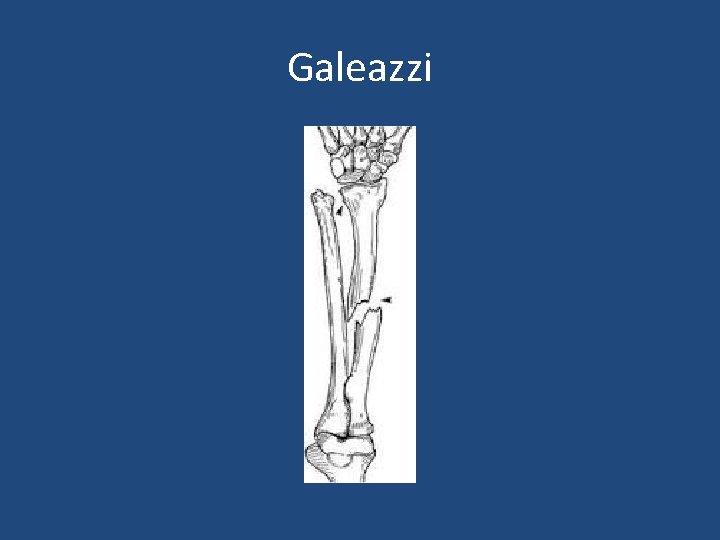

• Fractures are often from fall or direct blow. • Both bones fracture: – Means radius and ulna are broken. • Monteggia fracture: – Means proximal or middle third ulna shaft fracture with dislocation of radius proximally (at elbow) • Galeazzi fracture: – Means distal third shaft radius fracture with disruption of DRUJ.

Galeazzi

Galeazzi

Treatment • Both bone fracture: – Reduce and splint at ER/clinic (temporary) – Are treated almost always with ORIF: (plate and screws) • Monteggia fracture: – ORIF ulna and close reduction of radial head • Galeazzi fracture: – ORIF radius and close reduction of DRUJ.